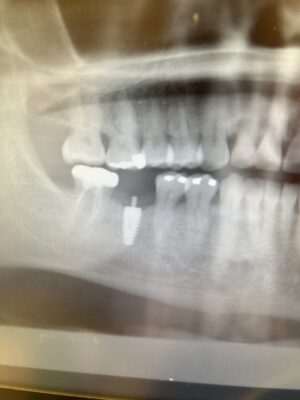

• So ive been dealing with this pt and wanted to get help with how to go about this complication. I placed a Neodent CM Dive in 2019 and the crown has come loose couple times. The thing will not unscrew completely and idk why that is and what can be done to remove the screw portion. It looks the abutment index broke off also. If i cannot remove…

Read more

• I kid you not I had another pt come in with same thing. This is the .9mm Neodent CM Drive implant. I mean what are the odd. 😭 Help!